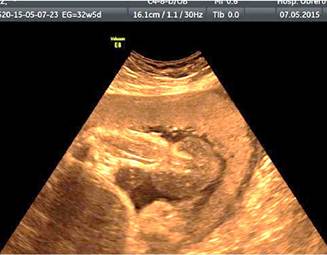

Acudió a control médico portando ecografía del tercer trimestre, que informaba: embarazo de 31 semanas, feto con una malformación en miembro inferior izquierdo que afecta tercio inferior de pierna, tobillo y pie (Edema vs Tumoración). Se practica segunda ecografía, esta vez, detallada en la Unidad de Medicina Fetal del Hospital Obrero N° 2 de la Caja Nacional de Salud - Cochabamba, que informó de un embarazo de 32 semanas con presencia de anillo constrictor en la unión de las 2/3 partes superiores de la pierna con el 1/3 distal, con edema distal importante (Figura 1), la vascularización distal conservada al momento del examen (Figura 2), concluyendo como: Síndrome de Brida amniótica con anillo constrictor en 1/3 inferior de pierna izquierda. La unidad de Medicina fetal recomendó mantener conducta expectante debido a la presencia de vascularización distal al anillo.